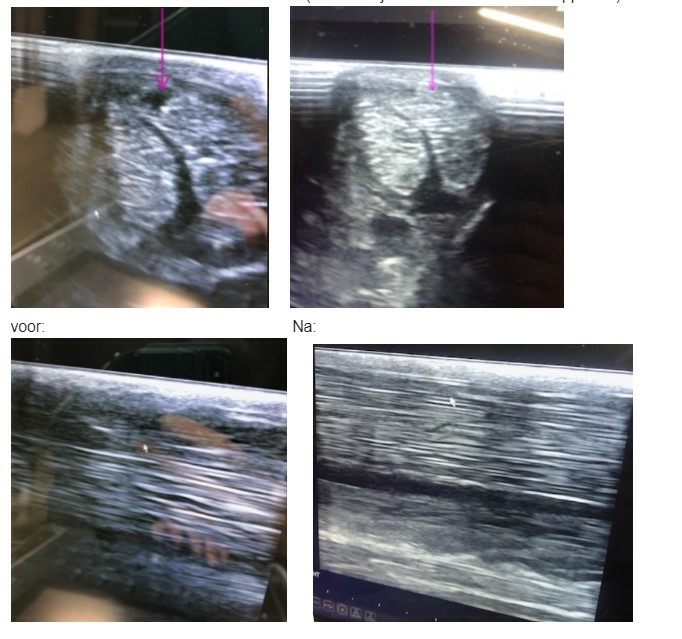

Bij twijfel is het altijd verstandig om een dierenarts in te schakelen. Met behulp van echografie kan de ernst van de blessure worden vastgesteld.

Het herstel van een peesblessure verloopt in fases en duurt vaak maanden tot een jaar. Een goed revalidatieschema bestaat meestal uit:

- Herstelfase – gecontroleerde training, aangepast aan de bevindingen op echo